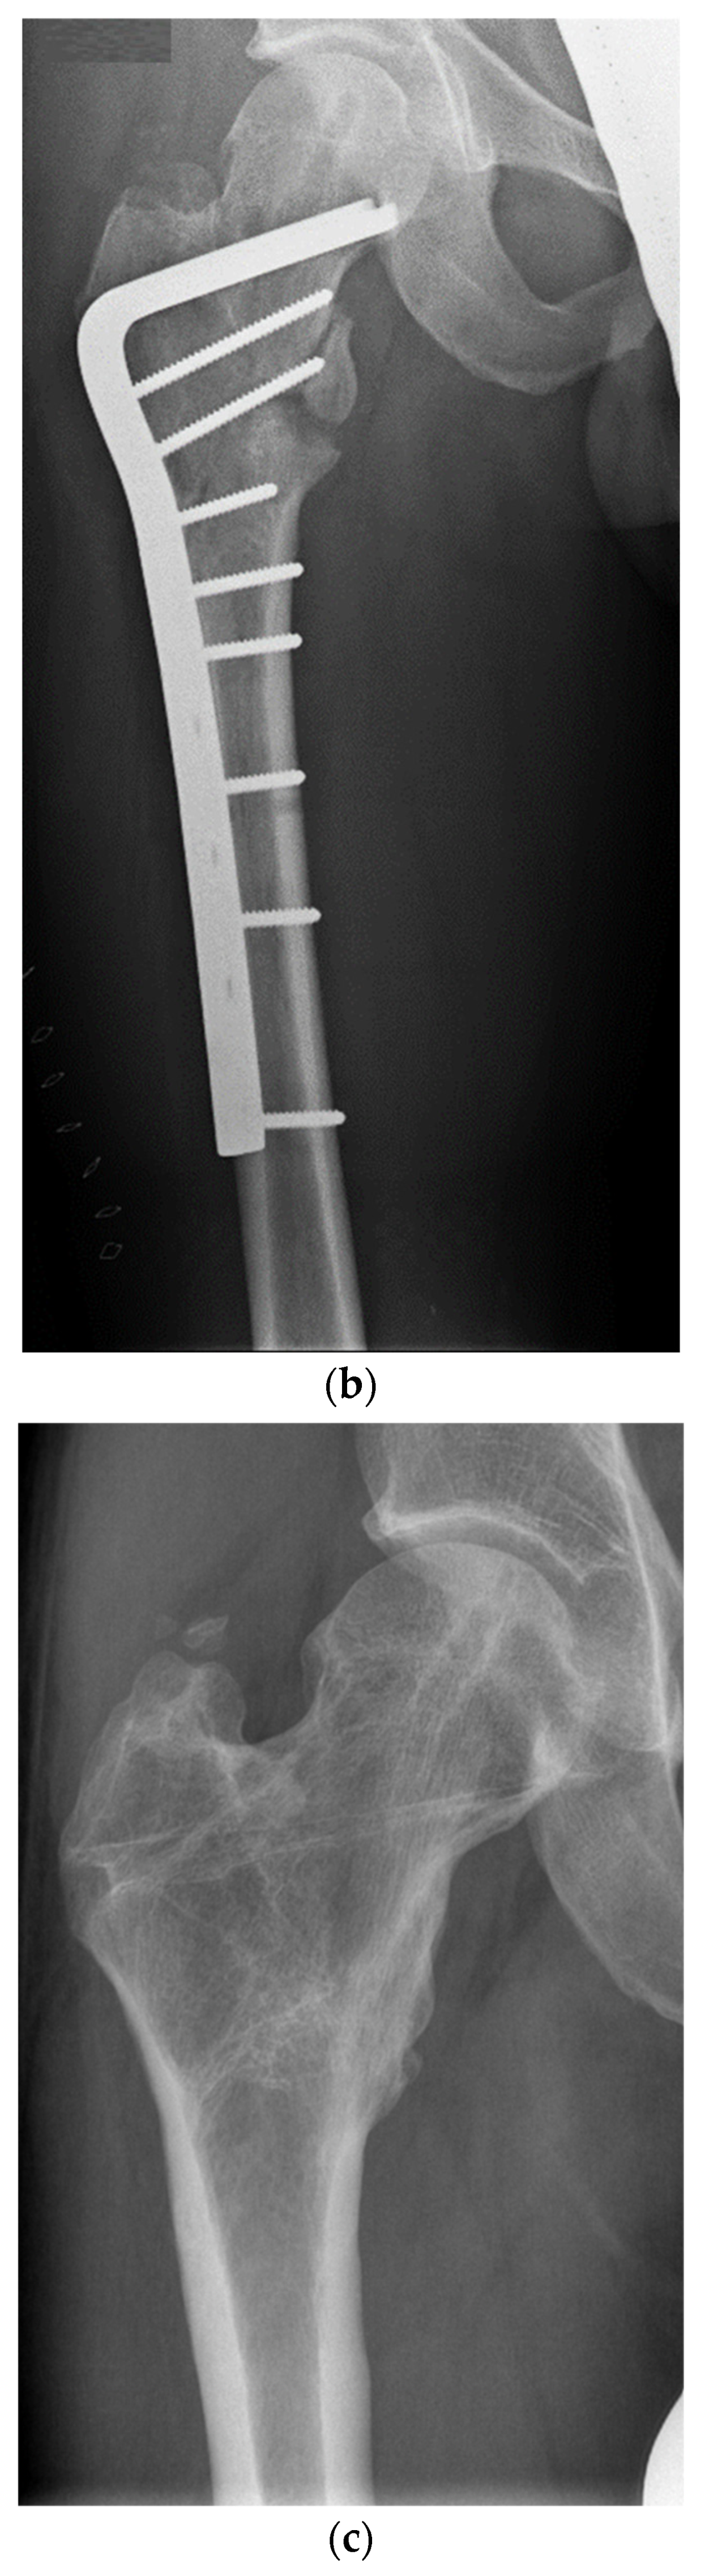

Functional and Radiological Results Following Revision Blade Plating and Cephalomedullary Nailing in Aseptic Trochanteric and Subtrochanteric Nonunion

2.2. Surgical Procedures